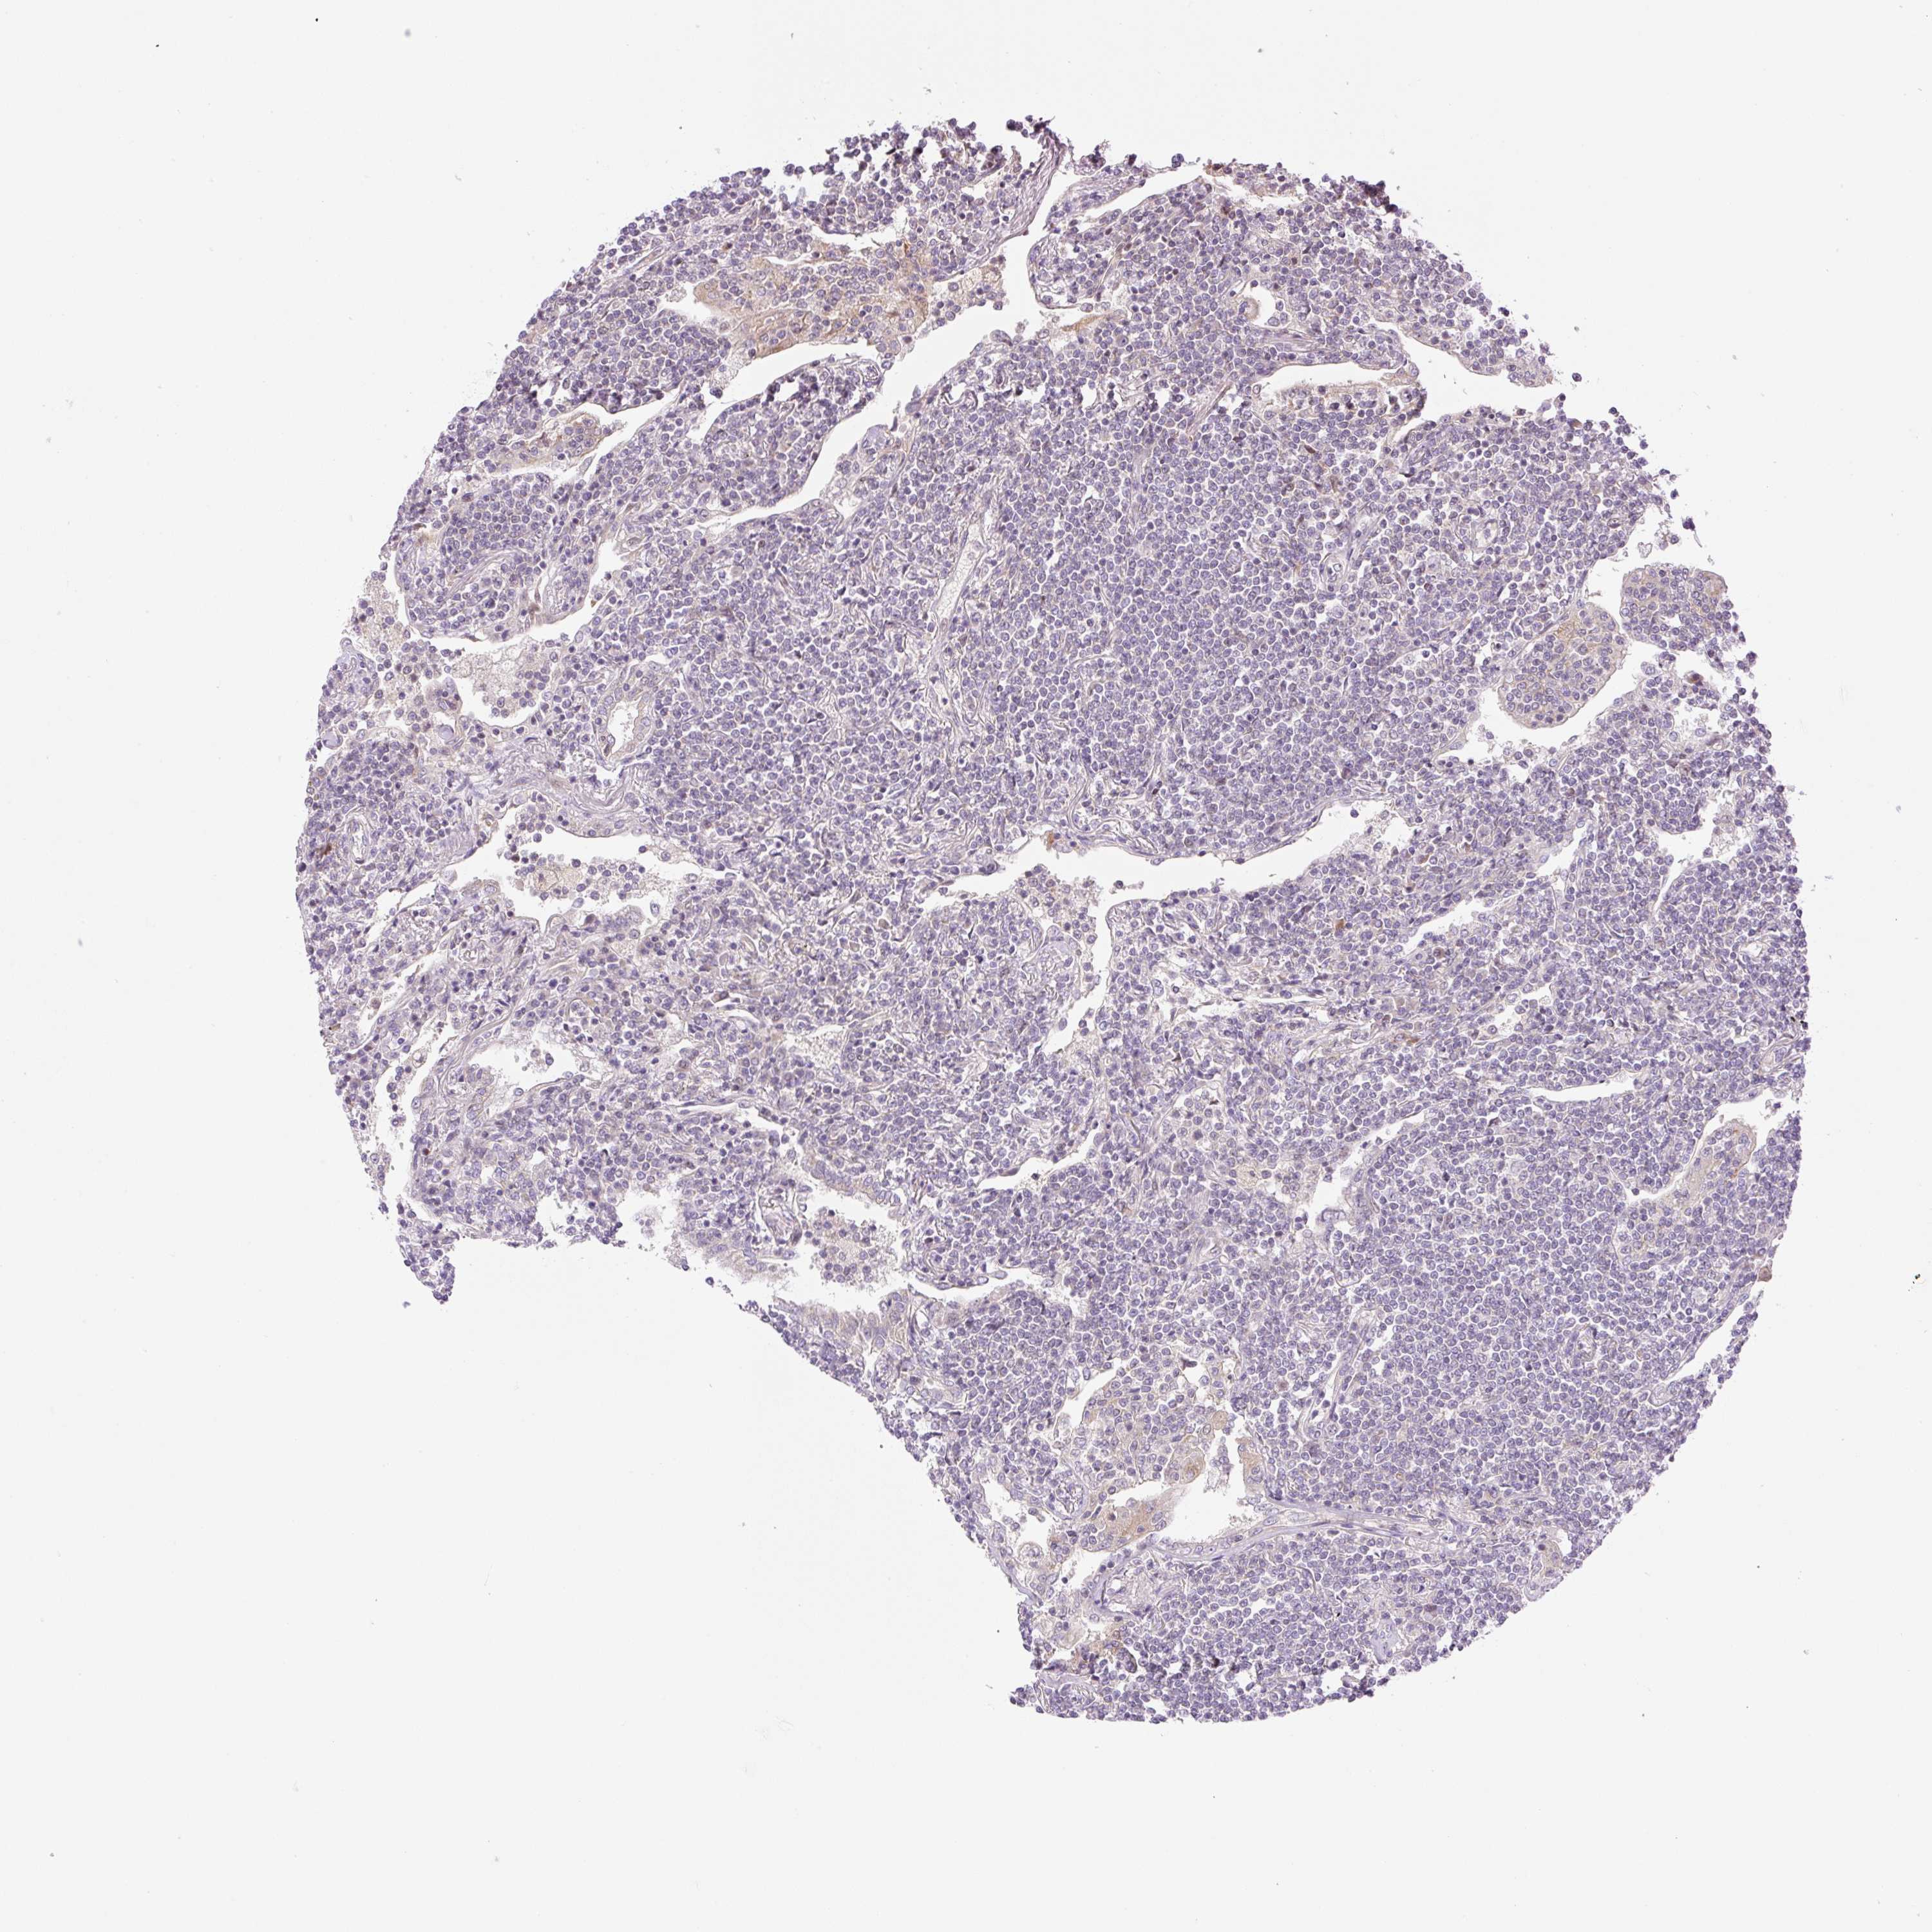

LYMPHOMA - Protein expressioni

A mouse-over function shows sample information and annotation data. Click on an image to view it in a full screen mode. Samples can be filtered based on level of antibody staining by selecting one or several of the following categories: high, medium, low and not detected. The assay and annotation is described here.

Antibody stainingi

Antibody staining in the annotated cell types in the current human tissue is reported as not detected, low, medium, or high, based on conventional immunohistochemistry profiling in selected tissues. This score is based on the combination of the staining intensity and fraction of stained cells.

Each image is clickable and will lead to virtual microscopy that enables deeper exploration of all samples and also displays staining intensity scores, fraction scores and subcellular localization as well as patient and tissue information for each sample.

Antibody HPA051421

Antibody HPA054639

Malignant lymphoma, non-Hodgkin's type, Low grade

Malignant lymphoma, non-Hodgkin's type, High grade

Hodgkin's disease, NOS